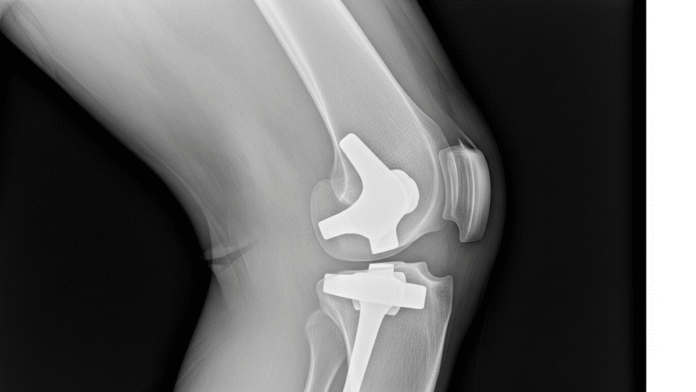

Prosthetic joint infections are a complication that can turn a successful joint replacement into a patient’s worst nightmare. With 45,000 PJI cases each year in the US and no approved therapeutics specifically indicated for this condition, patients face limited and often unsuccessful treatment options.

The challenge is growing as more joint replacement surgeries are expected. Projections show that by 2030, 3.48m knee and 572,000 hip replacements will be done each year in the US, each with a PJI risk that current medicine cannot fully manage.